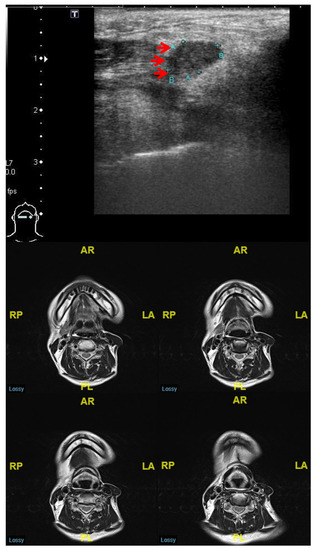

| Sonographic feature of lymphadenopathy | |

| Short axis (cm) | 1.07 ± 0.57 |

| Long axis (cm) | 1.66 ± 0.89 |

| S/L | 0.66 ± 0.16 |

| Margin (Clear/Vague) | 58 (56%)/46 (44%) |

| Internal echogenicity (Homo-/Hetero-geneous) | 47 (45%)/57 (55%) |

| Echogenicity (Hyper- or Iso-/Hypo-echogenicity) | 5 (5%)/99 (95%) |

| Calcification (Absent/Present) | 95 (91%)/9 (9%) |

| Architecture (Cystic/Solid) | 20 (19%)/84 (81%) |

| Echogenic hilum (Absent/Present) | 85 (82%)/19 (18%) |

| Vascular pattern (Hilar or Avascular/Others) | 88 (85%)/15 (15%) |